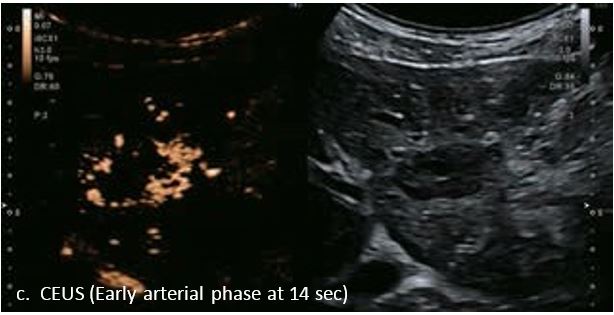

LI-RADS 4 множинні ГЦК

Це випадок 60-річної жінки з декомпенсованим цирозом печінки з асцитом. На сірошкальному зображенні можна виявити два вогнищевих ураження, розміром 21 мм і 10 мм відповідно, розташовані в сегменті 5. Оскільки дослідження методом зсувної хвилі на апараті Canon виконується штовхаючим імпульсом, пацієнтам з асцитом не можна проводити дослідження за допомогою зсувної хвилі, для визначення стадії фіброзу. На ранній артеріальній стадії гомогенне гіперехогенне підсилення спостерігається в обох ураженнях. Ураження є ізоехогенними в портальній венозній та пізній фазах, вимивання не спостерігається через 6 хвилин після ін'єкції, тому ці ураження були класифіковані як LI-RADS 4, ймовірна ГЦК. Важливо знати, що LI-RADS 5 - це ГЦК зі 100% вірогідністю, і вона не потребує біопсії. Значна кількість LI-RADS M (ймовірно або точно злоякісні, але не специфічні для ГЦК) і LI-RADS 4 (ймовірна ГЦК) насправді являються ГЦК.

Малюнок 11